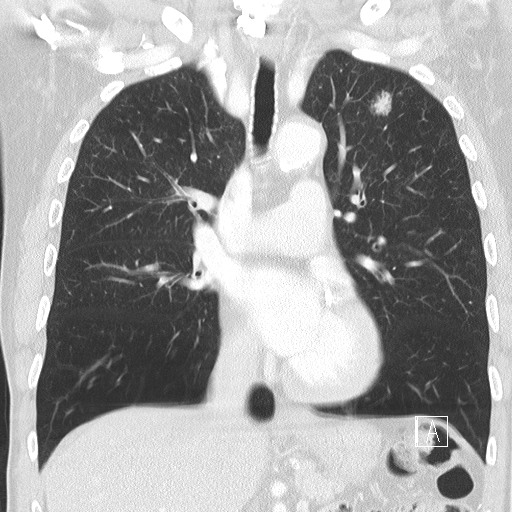

Pre-operative scan showing a tumour in Mr Ali's left lung

Mr Ali was diagnosed with lung cancer in the left lung and Mr Jordan performed a single port VATS lobectomy to remove the cancer.